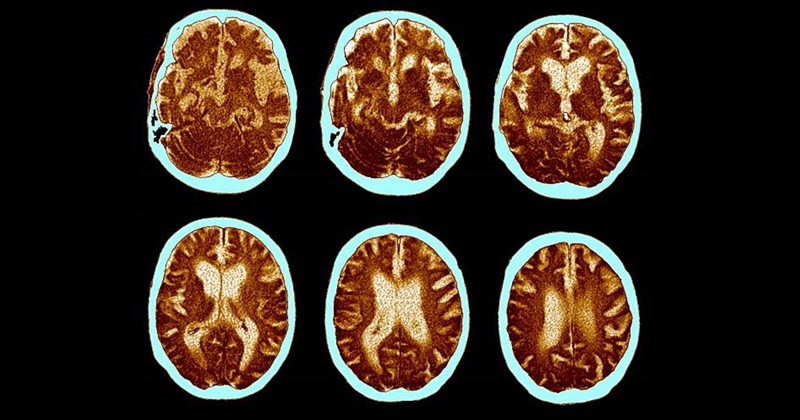

തലച്ചോറ് പ്രവര്ത്തനം പൂര്ണ്ണമായും അവസാനിപ്പിക്കുന്നതിന് മുമ്പ്, അതായത് ഒരു വ്യക്തിയുടെ മരണത്തിന് തൊട്ടുമുമ്പായി എന്താണ് തലച്ചോറില് നടക്കുന്നതെന്നും തലച്ചോറിന്റെ ശാസ്ത്രവും കണ്ടെത്താന് വളരെ കാലമായി ശാസ്ത്രജ്ഞര് ശ്രമിക്കുന്നു. മുമ്പ് മൃഗങ്ങളില് നടത്തിയ പഠനത്തില് ഹൃദയത്തിന്റെയും ശ്വാസകോശത്തിന്റെയും പ്രവര്ത്തനം നിലയ്ക്കുന്നതിന് തൊട്ടുമുമ്പ് തലച്ചോറില് ഗാമ തരംഗങ്ങള് വര്ധിച്ച സാന്നിധ്യം ഗവേഷകര് കണ്ടെത്തിയിരുന്നു.

എന്നാല്, മനുഷ്യരുടെ അന്ത്യസമയത്ത് തലച്ചോറിലുണ്ടാകുന്ന സംഭവവികാസങ്ങള് അടുത്തറിയുക എന്ന ലക്ഷ്യത്തോടെയാണ് അമേരിക്ക ആസ്ഥാനമായ മിഷിഗണ് സര്വ്വകലാശാലയിലെ ശാസ്ത്രജ്ഞര് വെന്റിലേറ്റര് സഹായം നീക്കിയതിന് ശേഷം, മരണത്തിലേക്ക് അടുത്ത നാലുപേരുടെ അവസാന സമയത്തെ ഇഇജി, ഇസിജി റിപ്പോര്ട്ടുകള് പഠനവിധേയമാക്കിയത്. ഈ നാലുപേരും കോമ അവസ്ഥയില് ആയിരുന്നു. രണ്ടു വ്യക്തികളില്, ഗാമ പ്രവര്ത്തനങ്ങള് കാരണം ഗ്ലോബല് ഹൈപ്പോക്സിയ സംഭവിച്ചതായി ഗവേഷകര് കണ്ടെത്തി. ഇവരുടെ കണ്ടെത്തലുകള് നാഷണല് അക്കാഡമി ഓഫ് സയന്സസില് പ്രസിദ്ധീകരിച്ചിട്ടുണ്ട്.